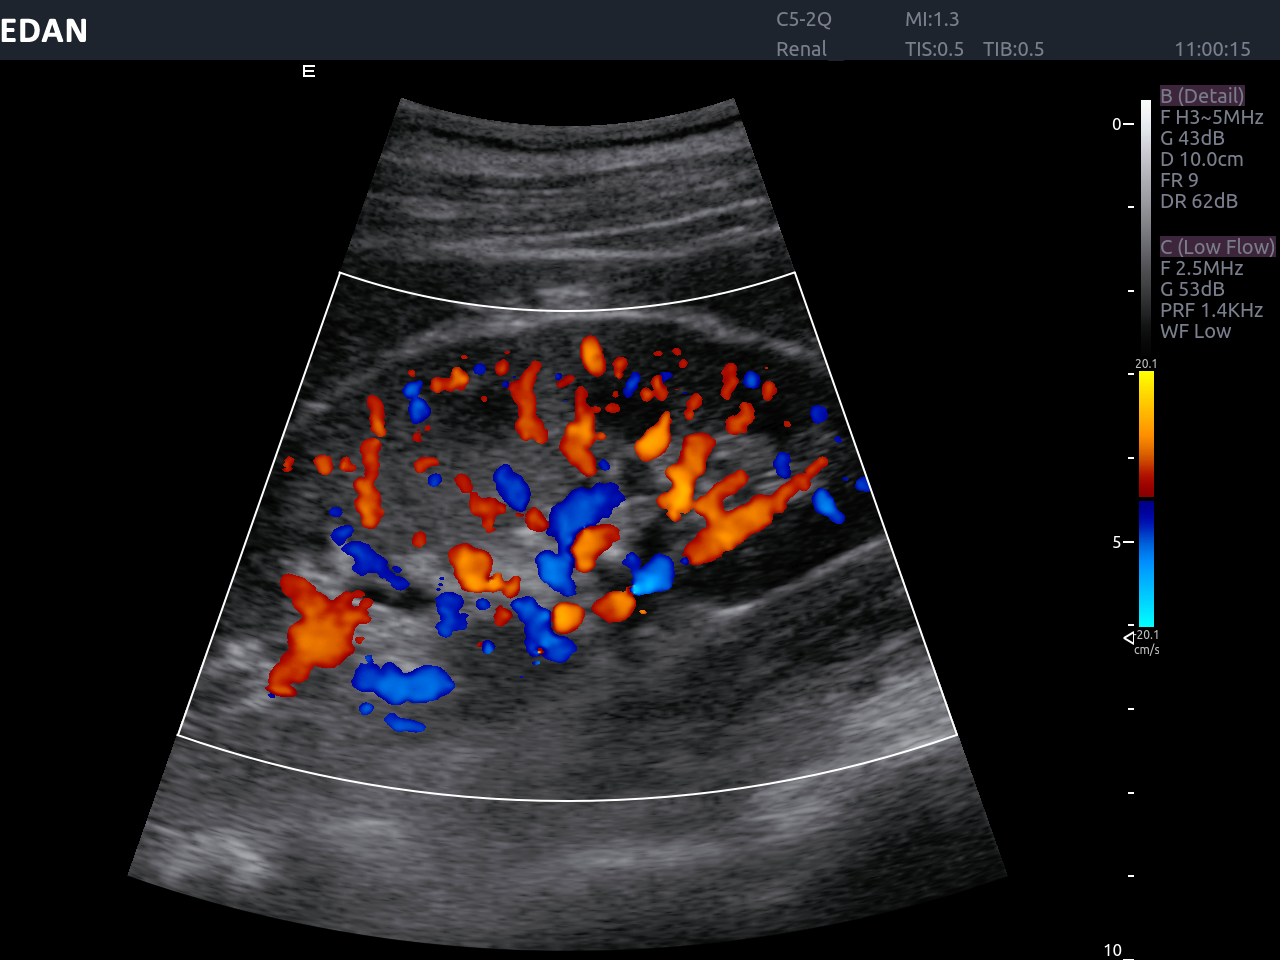

Educational workshops empower clinicians and technical staff with the knowledge needed to operate advanced ultrasound equipment effectively. The Acclarix LX8 incorporates eSRI (Enhanced Speckle Reduction Imaging), which employs real-time image processing to enhance visualization of anatomy and pathology. Proper training ensures that healthcare providers understand how to utilize this feature to reduce noise, improving diagnostic accuracy. Workshops enable staff to learn how to apply EDAN’s advanced multi-scale anisotropic filtering algorithm effectively, leading to clearer images and better outcomes.